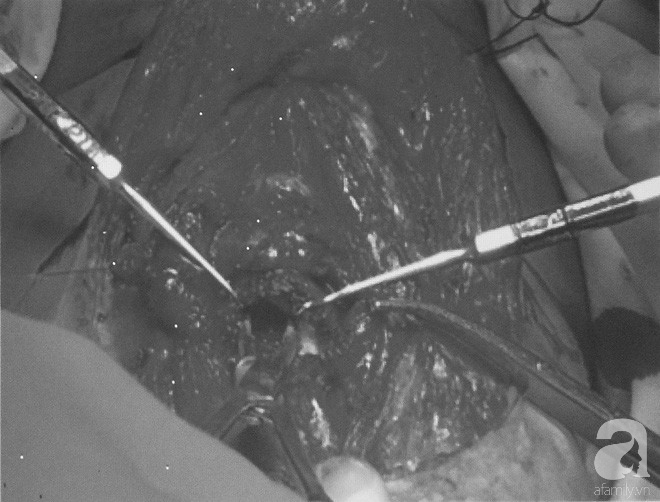

Các bác sĩ tiến hành phương pháp phẫu thuật cắt nối khí quản tận – tận cho bệnh nhân.

Ekip phẫu thuật cắt đoạn bị hẹp 5cm, bóc tách kéo hai đầu khí quản nối vào với nhau, khâu chỉ và nối lại. Ngày thứ 2 sau mổ, bệnh nhân được rút nội khí quản, đến ngày thứ 3 rút ống dẫn lưu, ngày thứ 7 rút ống nuôi ăn và khâu đóng cơ da.